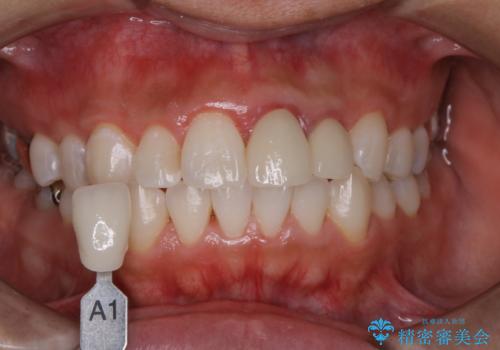

- 特に症状など気になるところはないが、メンテナンスして欲しいとのことでした。染め出しをしてのブラッシング指導とPMTC30分コースを行いました。

- 5,500円(税込)費用は治療当時の料金となります

- 歯を白くする目的の施術ではありません